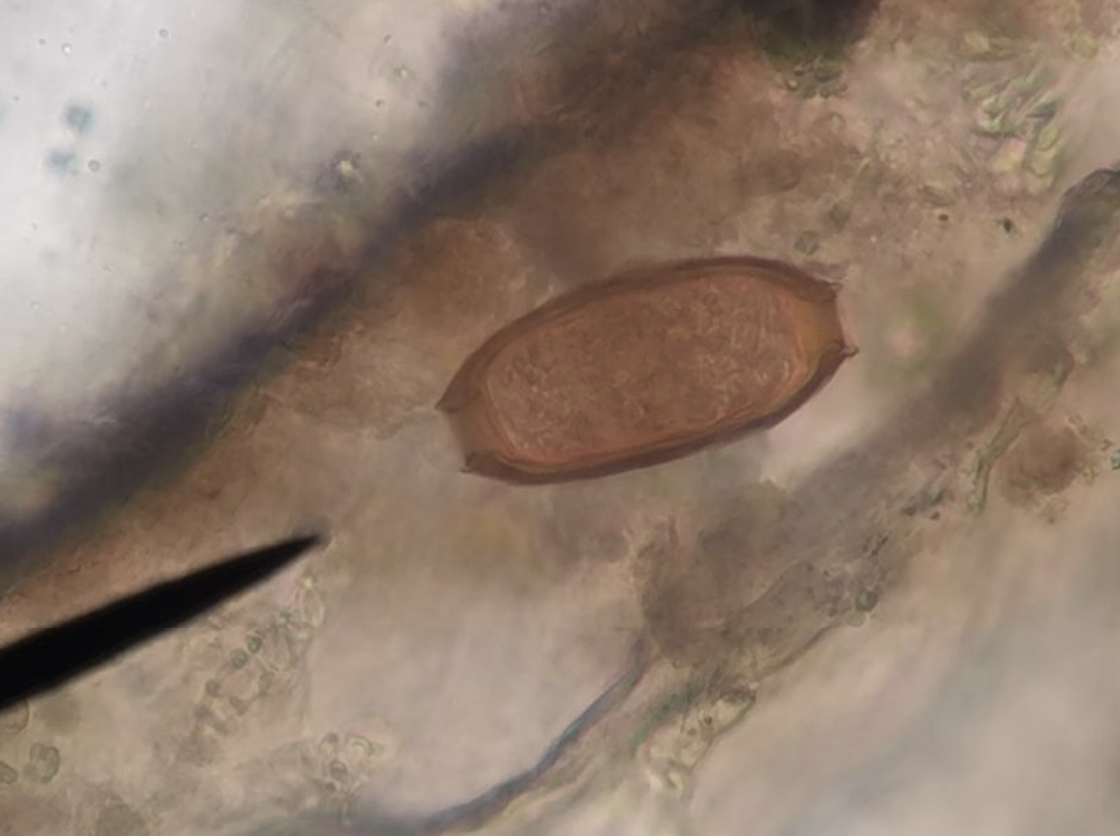

鞭虫卵

💡

纺锤状,壳厚,两端透明盖塞(安塞腰鼓!学起来就发狠了忘情了没命了!)4

虫卵呈纺锤形或腰鼓形, 大小(50~54)μm x (22~23)μm,棕黄色, 卵壳较厚,两端各有一透明塞状突起。虫卵随粪便排出时,卵内有1个尚未分裂的细胞。